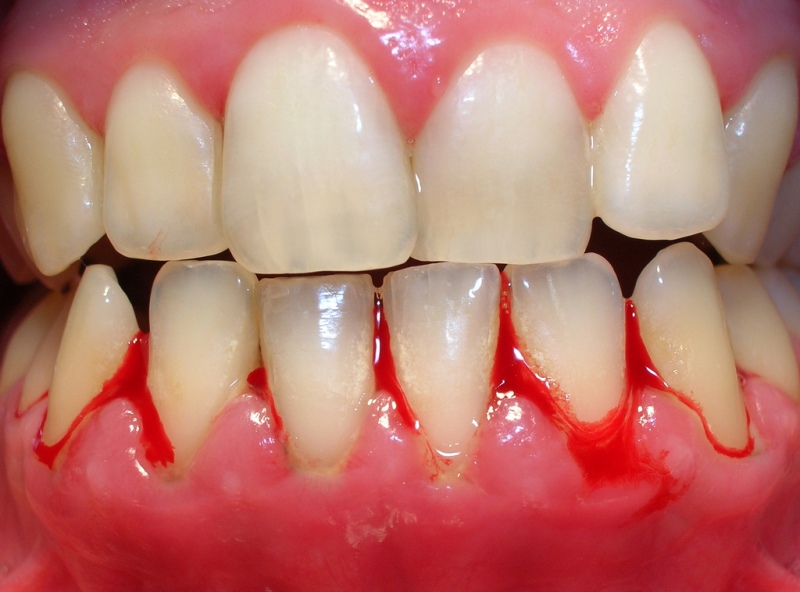

mesa de trabajo 3

Periodontitis